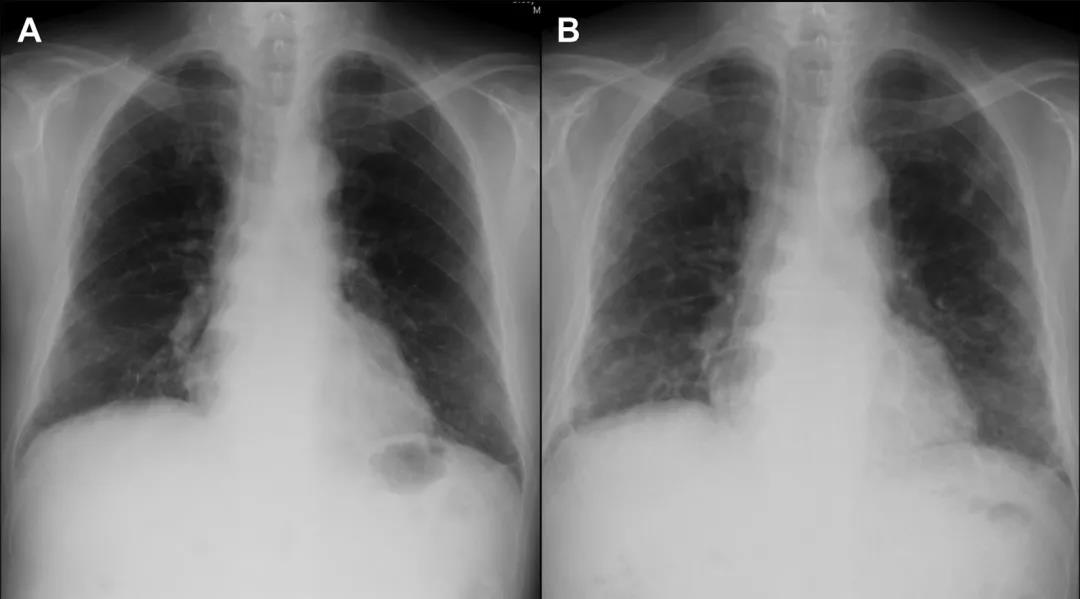

呼吸道症状曾一度有所缓解,但于入院第40天后死于呼吸衰竭。 简要病史 这是一个来自日本的病例:...